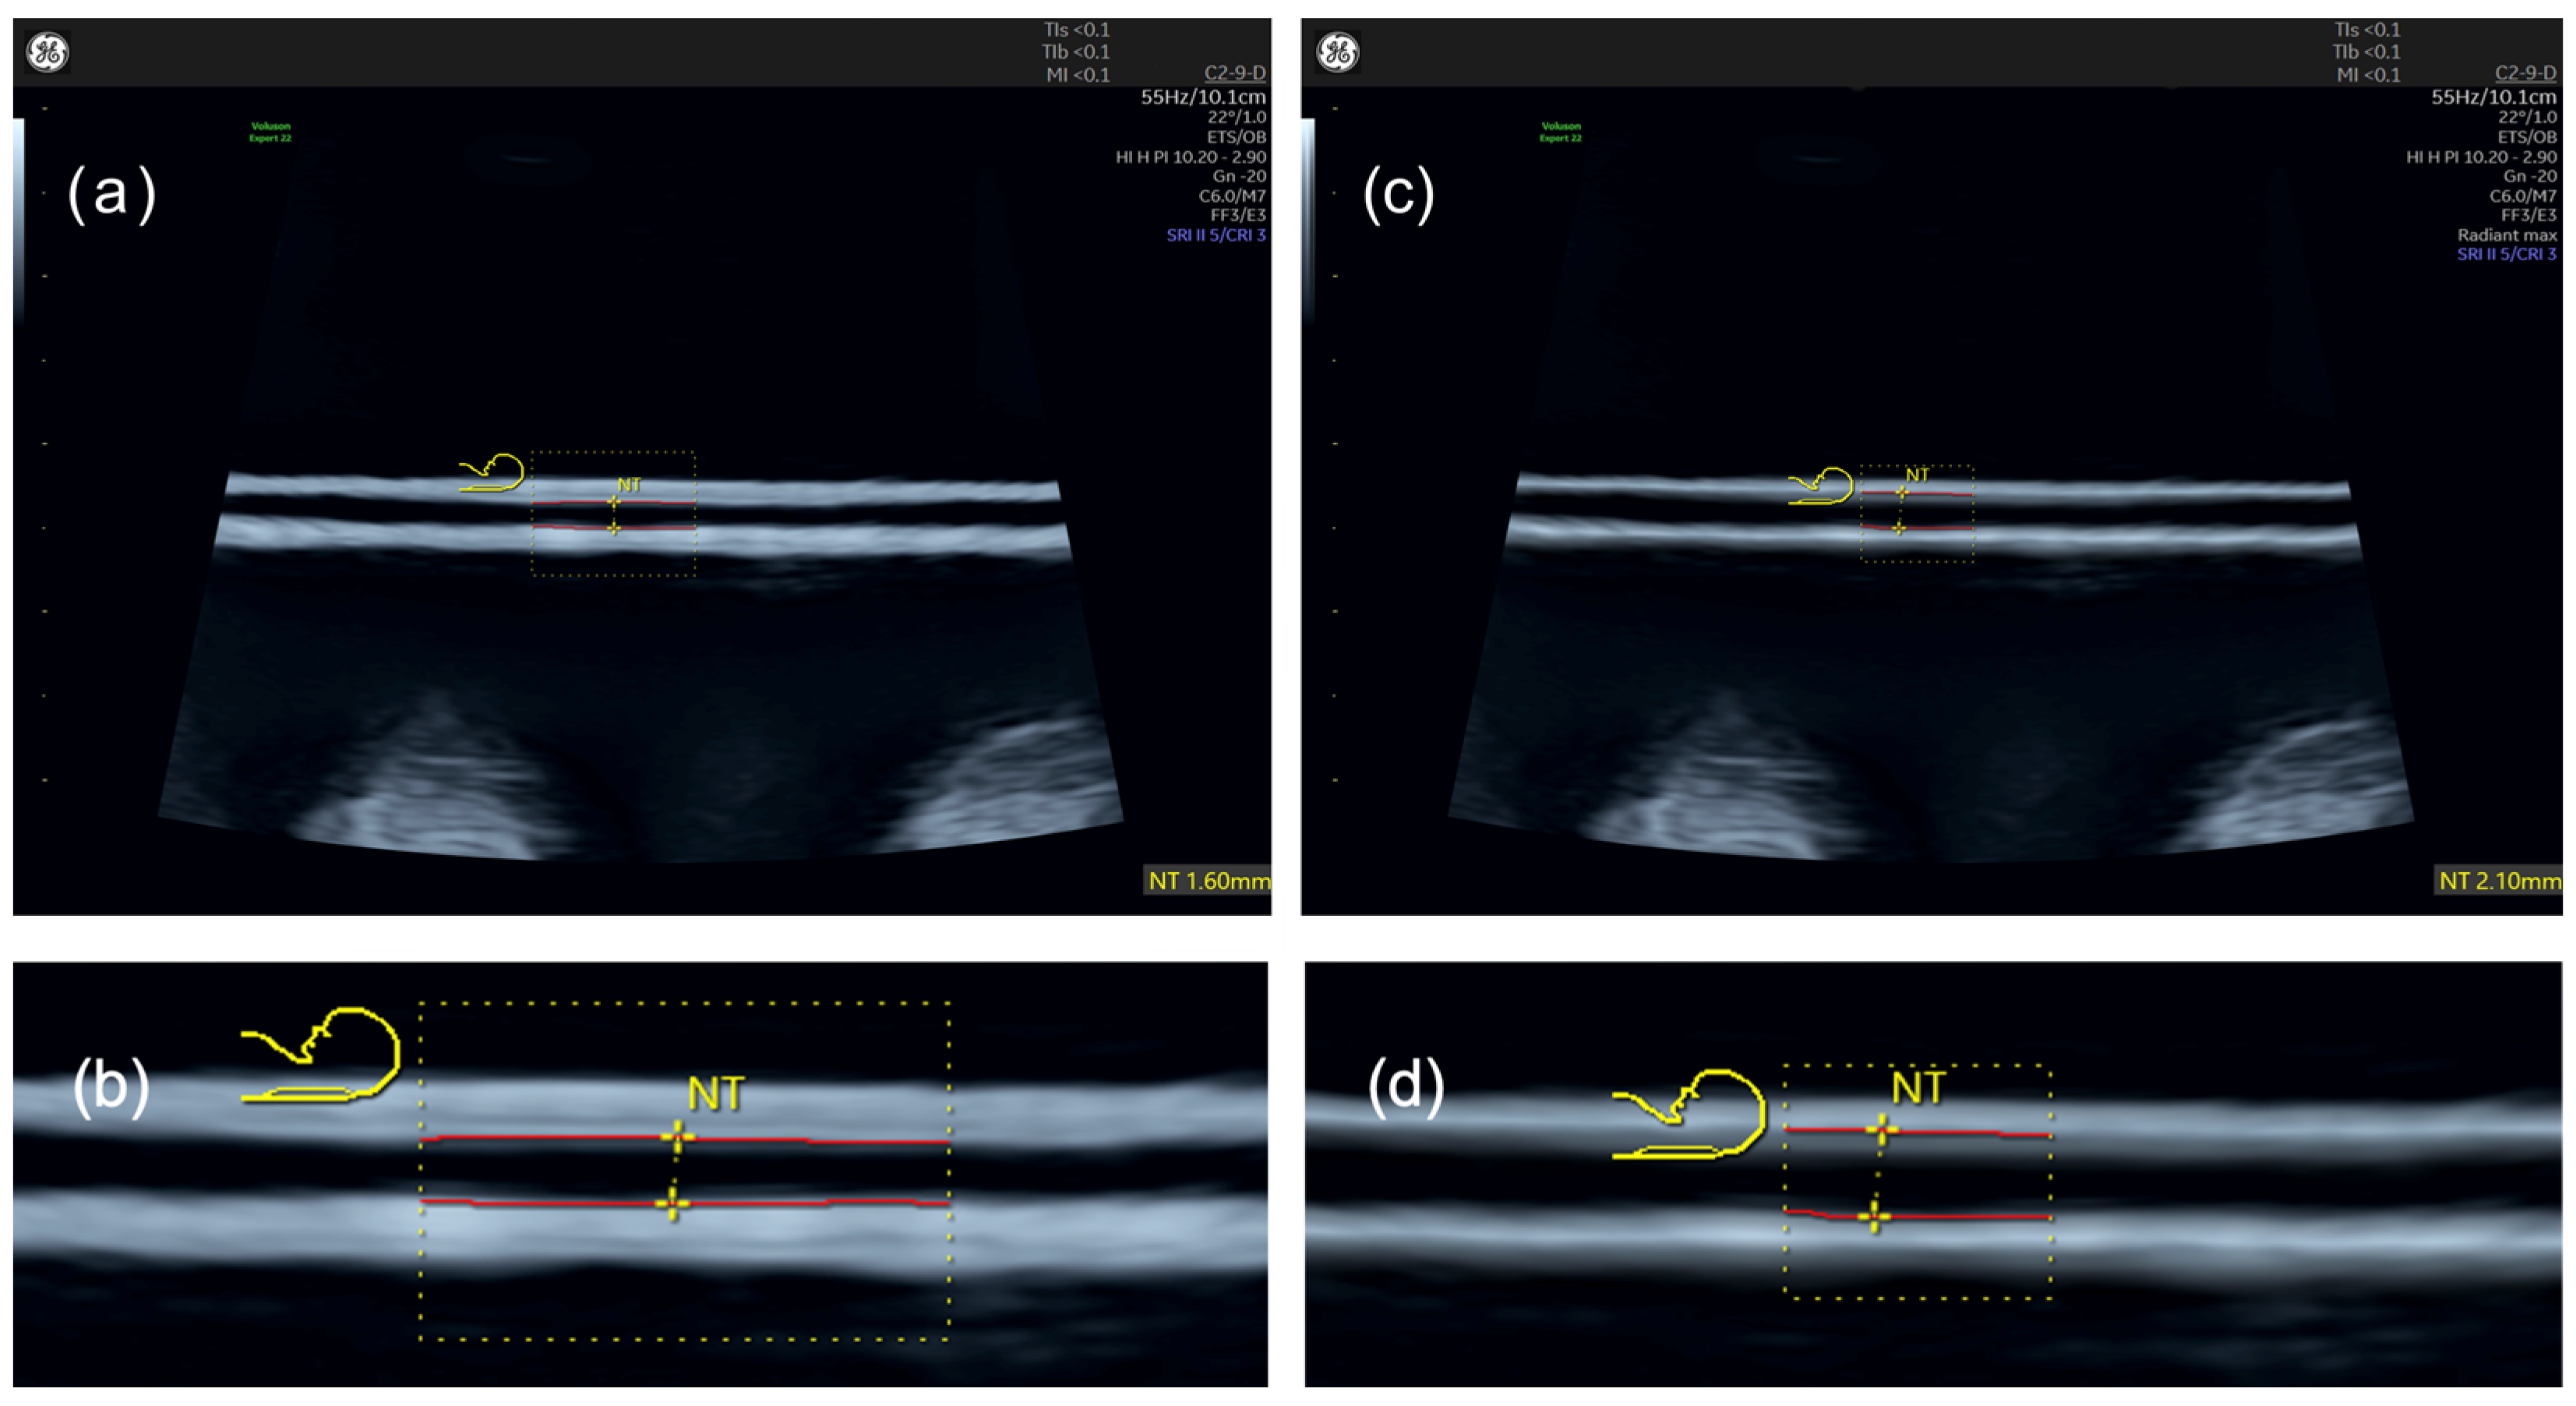

Nuchal Translucency with and without ‘Radiant’ Applied

3.1. Nuchal Translucency with and without ‘Radiant’ Applied